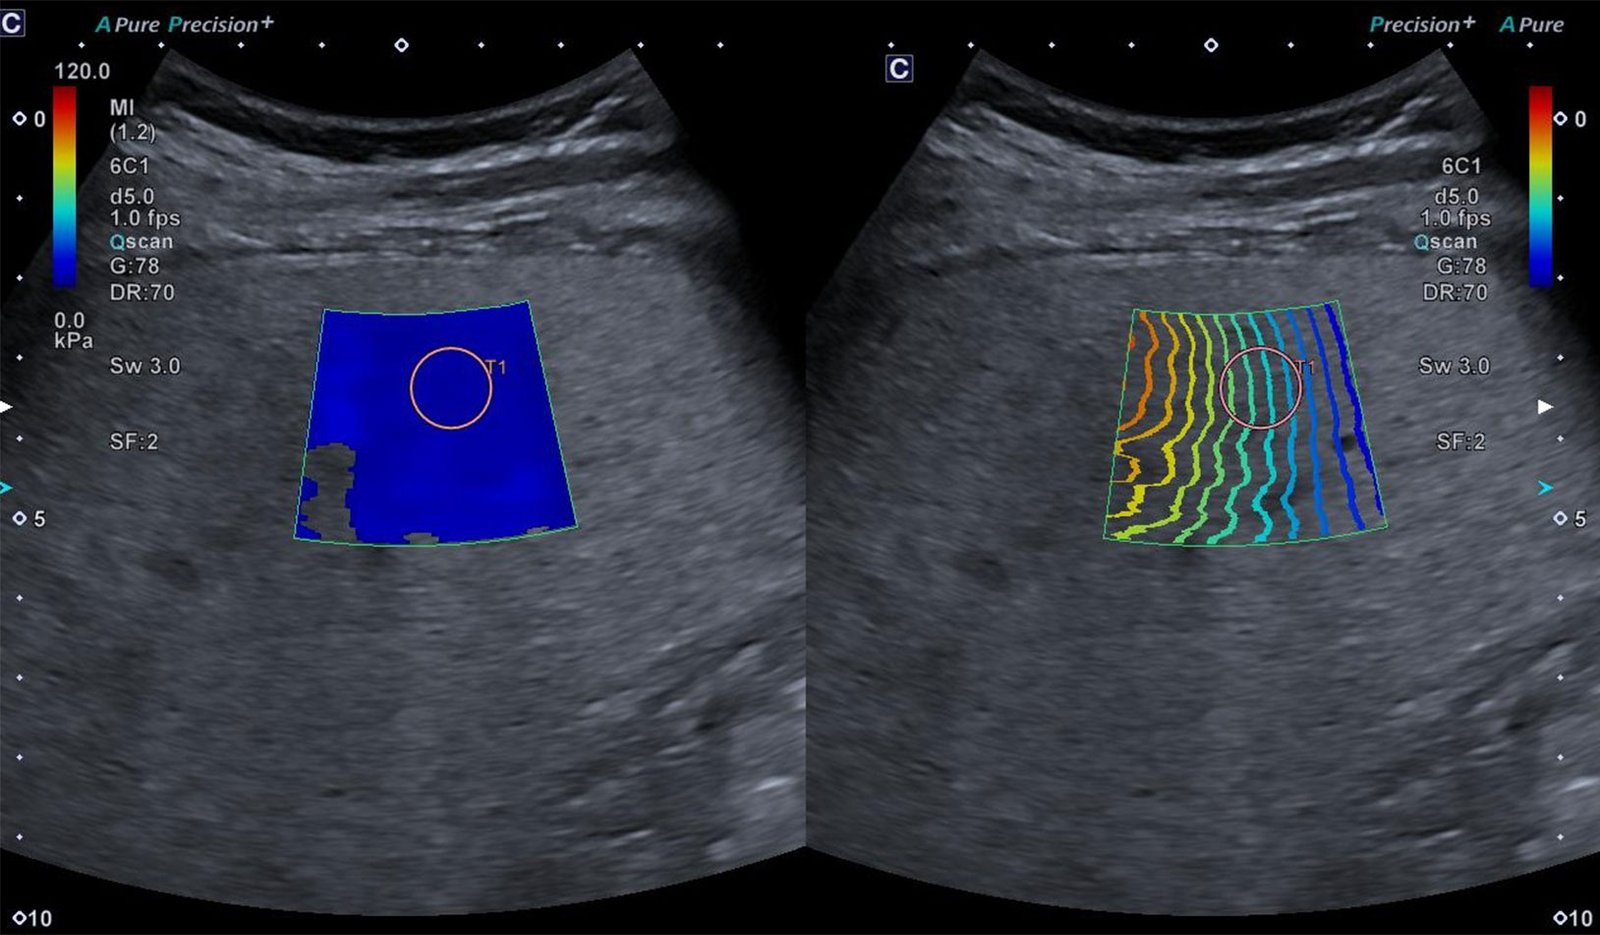

A elastografia hepática por ultrassonografia é um exame não invasivo, rápido e seguro que mede a rigidez do fígado (kPa/m/s) e estima a quantidade de gordura hepática, ajudando a estadiar fibrose e acompanhar a evolução de diversas doenças do fígado.

Realizo a elastografia em equipamento de última geração, com o software UMI, referência em elastografia e em atenuação/quantificação de gordura hepática.

Eu, Dra. Marina Taliberti, sou radiologista com mestrado em Radiologia e Diagnóstico por Imagem na área de Elastografia Hepática e aplico um protocolo padronizado, com interpretação integrada à história clínica e a outros exames. Meu propósito é transformar o exame em cuidado, oferecendo um laudo claro, técnico e útil para o médico assistente e para o paciente.

Durante o exame, é realizado um ultrassom do fígado com um software especial que emite pequenas ondas mecânicas e mede a rigidez do tecido hepático.

O resultado aparece em valores numéricos (em kPa ou m/s) que se correlacionam com os estágios de fibrose — desde ausência de fibrose até fibrose avançada/cirrose, de acordo com tabelas já validadas na literatura médica.